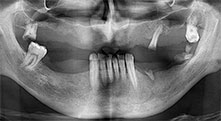

Bratu: We routinely use the instruments for harvesting bone blocks and splitting alveolar ridges. We also use the Piezomed B6/B7 for osteotomy of impacted teeth and removing failed implants. All indications that require deep, clean cuts.

Bratu: I consider piezo surgery a great leap forward in oral surgery. The technique makes bone preparation safer and easier. Little bone is lost, for example in extractions. This is very important in the aesthetic zone, particularly if immediate implantation is planned. Piezo surgery is also safer for soft tissue: injuries to membranes in the sinus are basically history, as are nerve injuries when bone blocks are being harvested. Data indicating reduced postoperative swelling and pain are also available. Piezo surgery is also ideal for preparation of sinus septa. And last but not least, our patients benefit from the atraumatic nature of this technology.